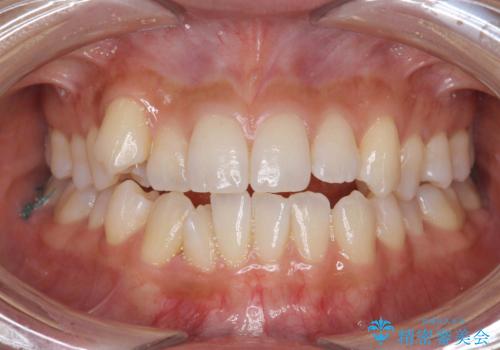

[マウスピース矯正] 海外留学中でも可能な矯正治療

担当医 大元洋佑

![[マウスピース矯正] 海外留学中でも可能な矯正治療の症例 治療前](https://seimitsushinbi.jp/wp/wp-content/uploads/2025/01/C4-1-500x350.jpg?v=1737343006)